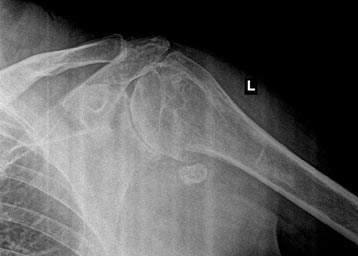

Bone of Bone Osteoarthritis of the Shoulder